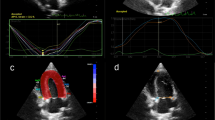

The PALS was significantly lower in the HCM group than the control group (P < 0.001). The longitudinal strain of LA regions was significantly reduced in the HCM group compared to the normal group, except the septal-roof and the lateral- roof of the LA (Table 3) (Fig. 1).

Two-dimensional speckle tracking echocardiography of the left apical four-chamber view was used to analyze the longitudinal deformation of the left atrium. Two-dimensional echocardiographic images were recorded at 100 frames/s for consecutive three cardiac cycles and three cineloops and stored these in the Digital Imaging and Communications in Medicine format. Offline analysis was performed in images with good quality from each cat. The LA wall, including the interatrial septum, the lateral wall and the atrial roof were tracked along during end-diastole. After automatic tracking, manual editing was performed to correct software errors in the region of interest. The ultrasound machine computer software (Strain 2.0 with Bull’s Eye) calculated the LA strain. The mean values of the measurements from three consecutive cardiac cycles were used in all analyses. Six segments were analyzed in each cat. The strain of each segment (as percentages) was plotted on the y-axis versus time (in seconds) on the x-axis over an entire cardiac cycle (Fig. 3). The different colored graphs represent strain curves from different segments. The white dotted line is the global strain. The QRS complex was used as the zero reference point, the peak positive longitudinal strain corresponds to the atrial reservoir function, the strain during early diastole represents atrial conduit function, and strain during late diastole corresponds to atrial contractile function. The peak atrial longitudinal strain (PALS) was the average of the peak of strain curves at the end of reservoir phase [8, 10]. The atrial strain rate was not analyzed in the present study.

The image of the left apical four-chamber view of the left atrial strain profile of a hypertrophic cardiomyopathy cat. A region of interest is manually drawn to include the left atrial wall. The automatic software system divided the left atrial wall into 6 different segments with different colors. A white dotted line is presented as the mean of strain value of the left atrium. LA=left atrium; LV= left ventricle; PALS= peak atrial longitudinal strain (white arrow); RA= right atrium; RV= right ventricle